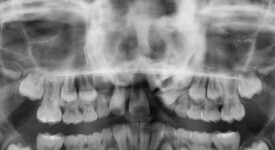

This is an example of a teenage patient with photographs of their smile before and after treatment at Braceline. Our orthodontic treatments are designed to provide maximum results in minimal time and to help you achieve the smile you always wanted!

Before Transformation!